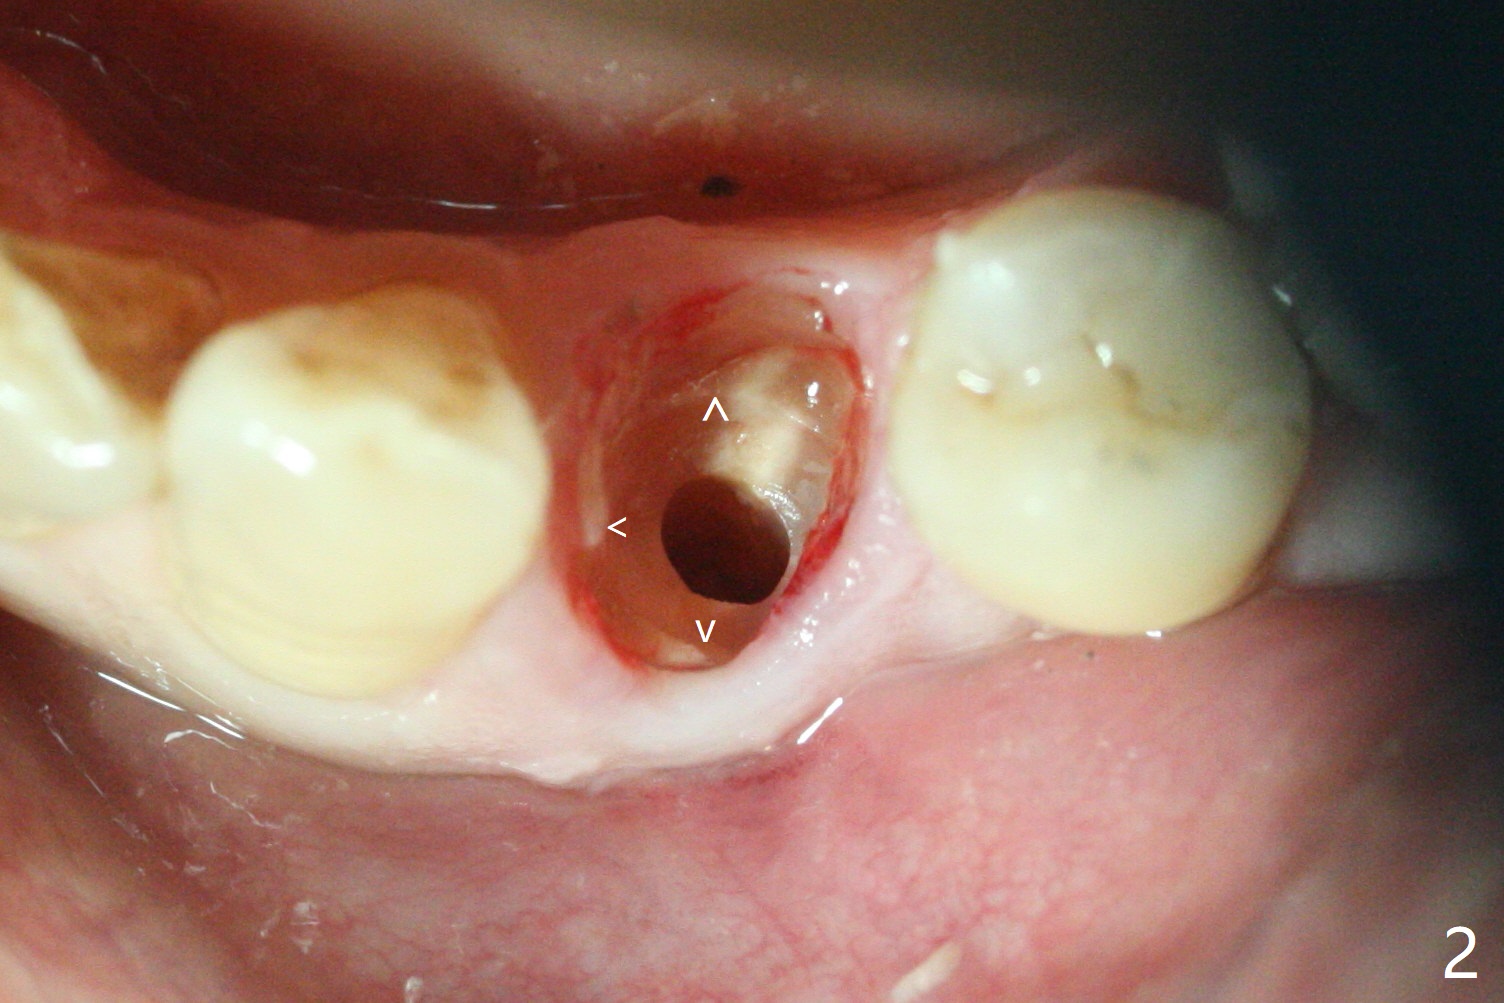

Three months post guide fabrication (coronavirus outbreak), the patient with loose post/crown returns for #21 extraction and immediate implant with guide (Fig.1 (*: post space)). In fact the root stump is flattened with diamond bur and 9 mm bone trimmer with guide before point drill. When the osteotomy finishes with 3.5x13 mm drill (under drilling with 10.5 mm offset), it has deviated buccal (Fig.2, 3,4); the outline of the bone trimmer mark is labeled by arrowheads in Fig.2. It appears that the center of the bone trimmer is dictated by that of the post space, as compared to Fig.1 *). When the root is removed except buccal shield (assuming that the deviation was due to the uneven surface of the root stump), the osteotomy is redone with guide, but remains buccal. Finally with buccal shield removal, a new lingual osteotomy is created free hand for a 4.5x11 mm implant (Fig.5) with 2-3 mm buccal gap for bone graft (Fig.6 * (literally)). In brief, bone trimmer also deviates according to resistance, basically irrelevant to the guide sleeve. The immediate provisional is intentionally removed 5 days postop to check whether a piece of gauze is retained in the socket as a gingival retraction cord for temporary crown fabrication; the buccal gap is kept with bone graft (Fig.7 *). No foreign body is in place. The margin of the abutment seems quite subgingival (Fig.8 *), but re-trimmed and polished provisional looks harmonious with the surrounding gingiva and the opposing dentition (Fig.9,10). The patient returns for prophy 2 months postop; the immediate provisional is removed for trimming and polishing. The bone graft seems to be integrated into a part of the gingiva (Fig.11 >). The abutment cuff appears to be too short.